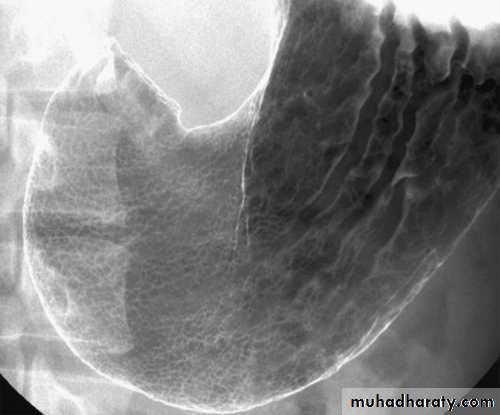

Normal appearance of the small bowel

• The normal SB occupies the central & lower abdomen.• The terminal ileum enters the medial aspect of the cecum through the ileocecal valve.

• Normal mucosa exhibit a feathery appearance [Valvulae conniventes].

• The diameter of SB loop should not exceeds 3 cm .

• Jejunum is wider than the ileum.

• Valvulae conniventes is conspicuous at jejunum more than the ileum.